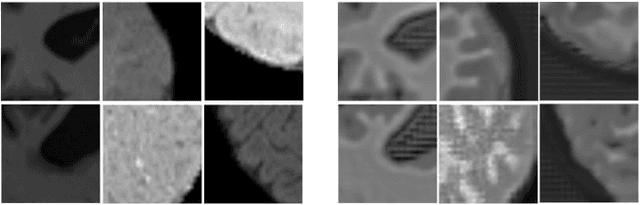

Abstract:Image normalization is a building block in medical image analysis. Conventional approaches are customarily utilized on a per-dataset basis. This strategy, however, prevents the current normalization algorithms from fully exploiting the complex joint information available across multiple datasets. Consequently, ignoring such joint information has a direct impact on the performance of segmentation algorithms. This paper proposes to revisit the conventional image normalization approach by instead learning a common normalizing function across multiple datasets. Jointly normalizing multiple datasets is shown to yield consistent normalized images as well as an improved image segmentation. To do so, a fully automated adversarial and task-driven normalization approach is employed as it facilitates the training of realistic and interpretable images while keeping performance on-par with the state-of-the-art. The adversarial training of our network aims at finding the optimal transfer function to improve both the segmentation accuracy and the generation of realistic images. We evaluated the performance of our normalizer on both infant and adult brains images from the iSEG, MRBrainS and ABIDE datasets. Results reveal the potential of our normalization approach for segmentation, with Dice improvements of up to 57.5% over our baseline. Our method can also enhance data availability by increasing the number of samples available when learning from multiple imaging domains.

Abstract:Image normalization is a critical step in medical imaging. This step is often done on a per-dataset basis, preventing current segmentation algorithms from the full potential of exploiting jointly normalized information across multiple datasets. To solve this problem, we propose an adversarial normalization approach for image segmentation which learns common normalizing functions across multiple datasets while retaining image realism. The adversarial training provides an optimal normalizer that improves both the segmentation accuracy and the discrimination of unrealistic normalizing functions. Our contribution therefore leverages common imaging information from multiple domains. The optimality of our common normalizer is evaluated by combining brain images from both infants and adults. Results on the challenging iSEG and MRBrainS datasets reveal the potential of our adversarial normalization approach for segmentation, with Dice improvements of up to 59.6% over the baseline.